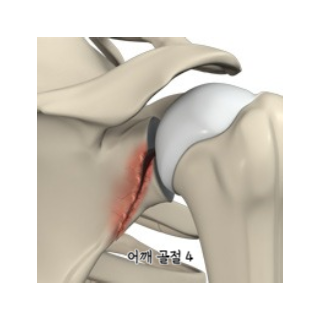

1.1 회전근개 손상

회전근개는 어깨 관절을 둘러싼 근육과 건의 집합체로, 어깨의 안정성과 운동성을 담당합니다. 어깨와 팔을 연결하는 4개의 근육(극상근, 극하근, 소원근, 겹갑하근) 및 힘줄로 이루어져 있습니다. 회전근개 손상은 반복적인 움직임, 과도한 사용, 또는 외상으로 인해 발생할 수 있습니다. 간혹, 회전근개 손상을 오십견으로 생각하고 방치하다 치료가 늦어지는 경우가 있어 주의가 필요합니다.

회전근개 손상은 다양한 원인에 의해 발생할 수 있으며, 주로 과도한 사용, 퇴행성 변화, 외상 등이 원인으로 꼽힙니다. 구체적인 원인은 다음과 같습니다.

회전근개 손상의 증상

- 어깨 외측 부위의 통증

- 팔을 들어올리거나 옆으로 벌리는 동작 시 통증 악화

- 어깨 근력 약화 및 운동 범위 제한